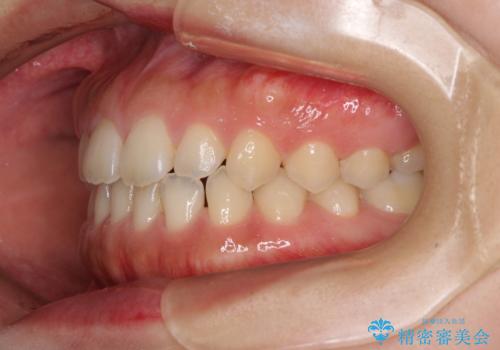

気になる隙間の再矯正 前歯をインビザライン・ライトで改善

- 後戻りによる上下前歯の隙間を気にして来院された患者様です。

歯列不正はそれほど大きくなかったため、インビザライン・ライトを用いて矯正治療を行うこととしました。

無理のないペースで治療を進め、9ヶ月で終えることができました。